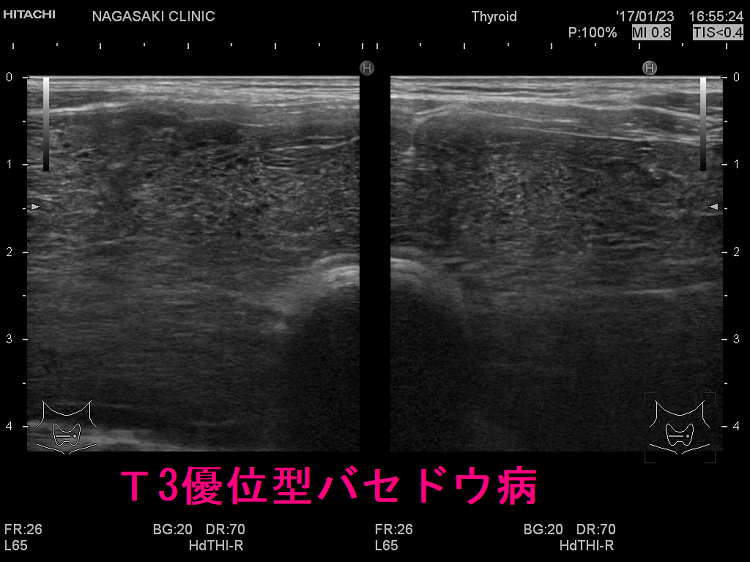

ケース② 巨大甲状腺腫・甲状腺内部血流増大

ケース③ 異常に太い下甲状腺動脈

T3優位型バセドウ病の異常に太い下甲状腺動脈。総頚動脈とほぼ同じ太さで、赤・青・黄が混じった乱流になっています。下甲状腺動脈血流速度(ITA-PSV)も異常に高く、186cm/sでした。